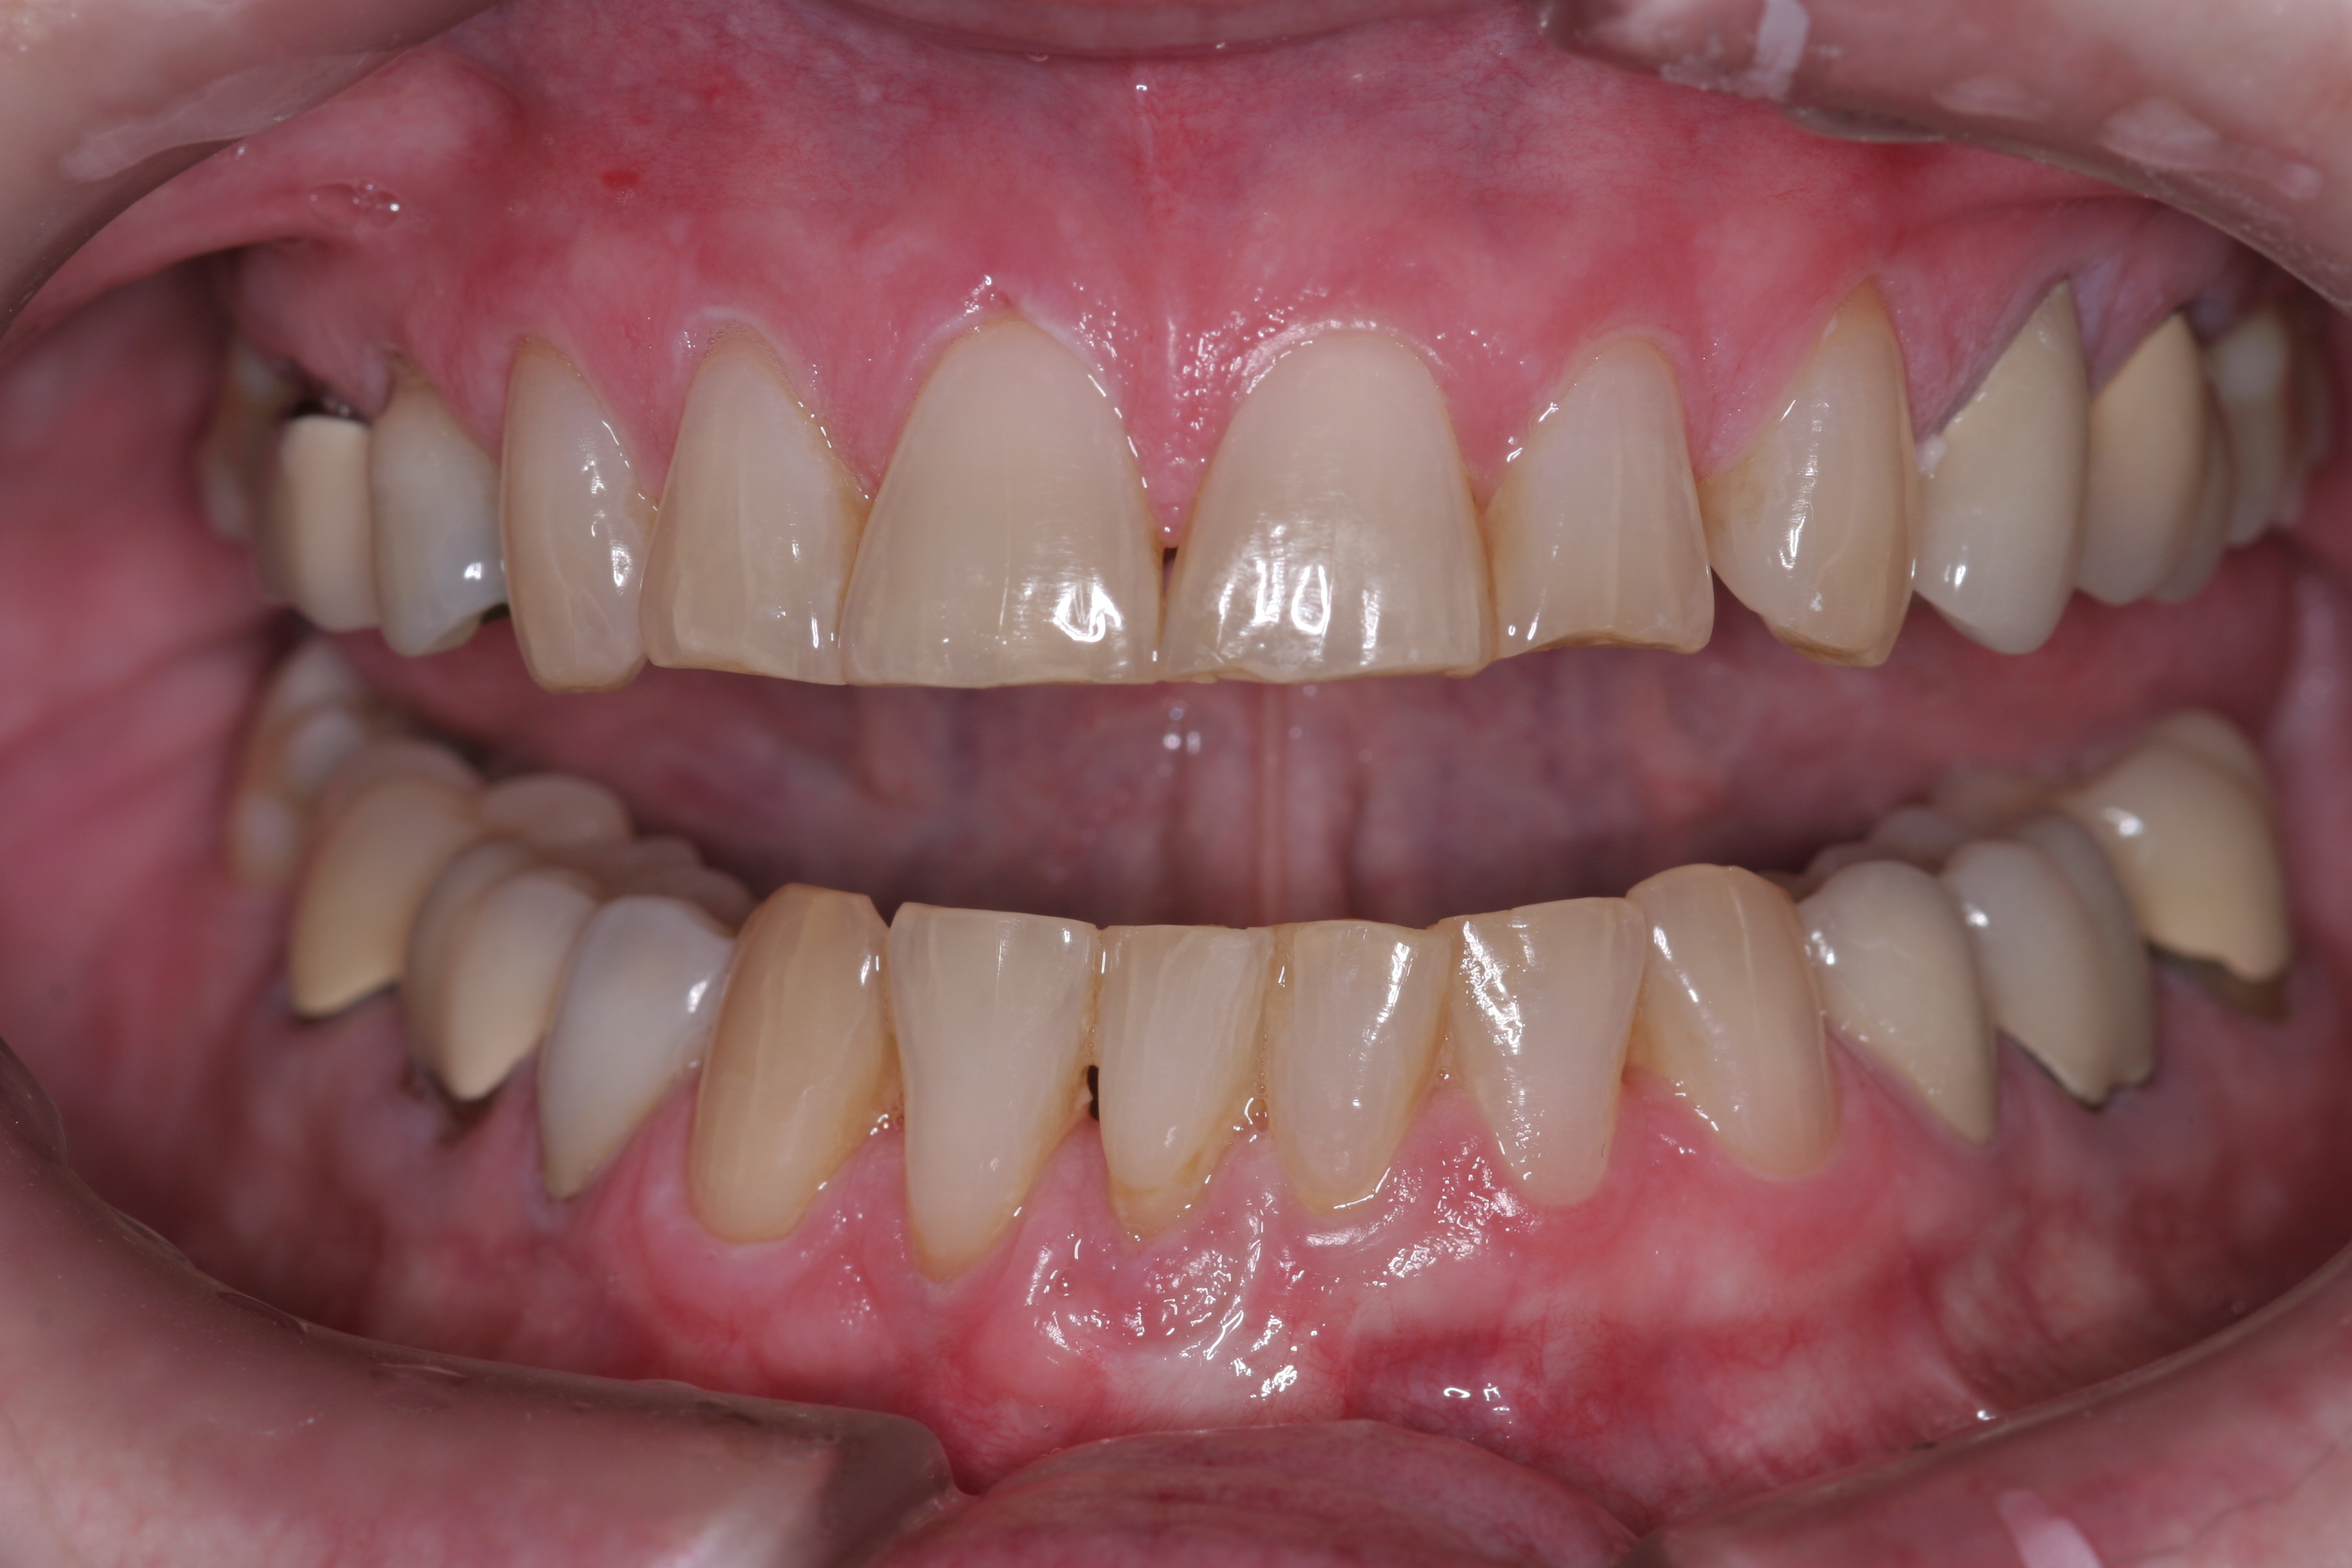

A patient presented with advanced generalized wear of her anterior teeth (Figure 10 and Figure 11). She was displeased with their overall appearance because of their color and wear (Figure 12). A complete examination was performed, revealing instability in her temporomandibular lateral poles bilaterally, sore muscles of mastication, advanced wear, a CR/MIP discrepancy, and loss of her anterior guidance due to the wear. Although the topic is beyond the scope of this article, the patient was also screened for possible sleep apnea. This included an evaluation of the Mallampati score, previous sleep therapy evaluation or treatment, snoring history, an evaluation of her neck size, her weight status, and the presence of the tonsils and their size. In every case, if this clinician suspects airway obstruction to be playing a role in tooth wear issues, the patient is referred to a sleep physician. The patient in this case displayed few apnea risk factors, and the patient’s anterior wear facets fit together like a “lock and key” pattern seen in parafunctional activity. Splint therapy was initiated to stabilize the joints and muscles. A repeatable CR position was verified through load testing. At this point diagnostic models, photographs, a CR bite record, and a facebow were taken and recorded.

(11.) A patient presented with advanced generalized wear of her anterior teeth, and was displeased with their overall appearance because of their color and wear.

Figure 11

(12.) A patient presented with advanced generalized wear of her anterior teeth, and was displeased with their overall appearance because of their color and wear.

Figure 12

For instance, the patient in Figure 9 has lost nearly 40% to 50% of his maxillary anterior tooth structure, yet the teeth are still in full intercuspation due to continued eruption as tooth structure is lost due to wear. As wear occurs on the lingual aspects of maxillary anterior teeth, teeth drift to the lingual, which constricts the envelope of function. Wear on the lower incisors can lead to super eruption, which increases the overjet/overbite relationship. Both of these alterations in tooth position steepen the anterior guidance and are less than desirable situations with patients with worn dentitions.

(9.) This patient has lost nearly 40% to 50% of his maxillary anterior tooth structure, yet the teeth are still in full intercuspation due to continued eruption as tooth structure is lost due to wear.

Figure 9